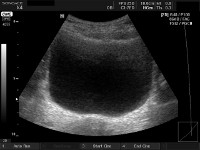

Ultrasound of the bladder to a child.

УЗИ мочевого пузыря у ребенка проводится через переднюю брюшную стенку (трансабдоминально) с использованием многопозиционного сканирования с максимальным естественным наполнением мочевого пузыря. При необходимости возможно заполнение мочевого пузыря стерильным физиологическим раствором путем катетеризации. Процесс сканирования мочевого пузыря оценивает его размеры, толщину стенки, содержимое и патологические изменения. В детской урологии показания к УЗИ мочевого пузыря могут быть болезненными, изменения в моче, недержание мочи, боли в животе.

Обычно мочевой пузырь располагается как безэховая формация округлой формы, расположенная в полости таза, с ровными контурами и стенками одинаковой толщины. Объем остаточной мочи после опорожнения мочевого пузыря не должен превышать 10 мл. Наличие асимметрии мочевого пузыря, изменения трабекулярности и толщины стенки, кистозных структур и объемных поражений в полости мочевого пузыря по данным УЗИ расцениваются как патология.